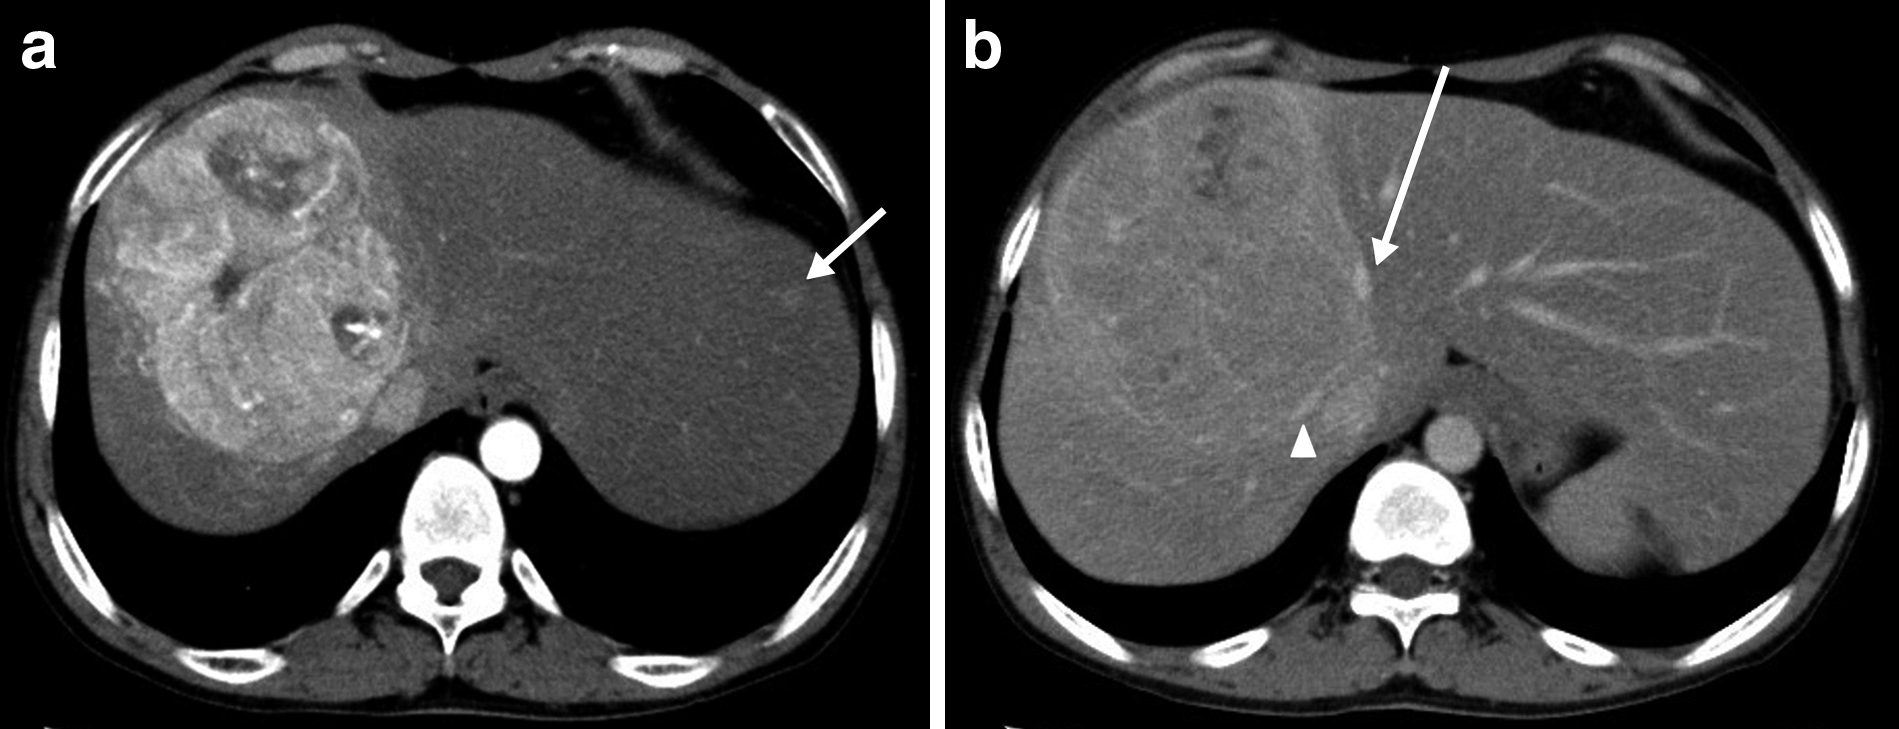

術前CT所見:腫瘍は径7 cmに縮小し,主要血管の圧排所見が改善した(Fig. 2).肝S2の小病変は画像上指摘できなくなった.全肝容積は2,805 mlと肝腫大を認めた.

Enhanced CT findings before surgery. The tumor does not displace the right hepatic vein (arrowhead) and middle hepatic vein (arrow).